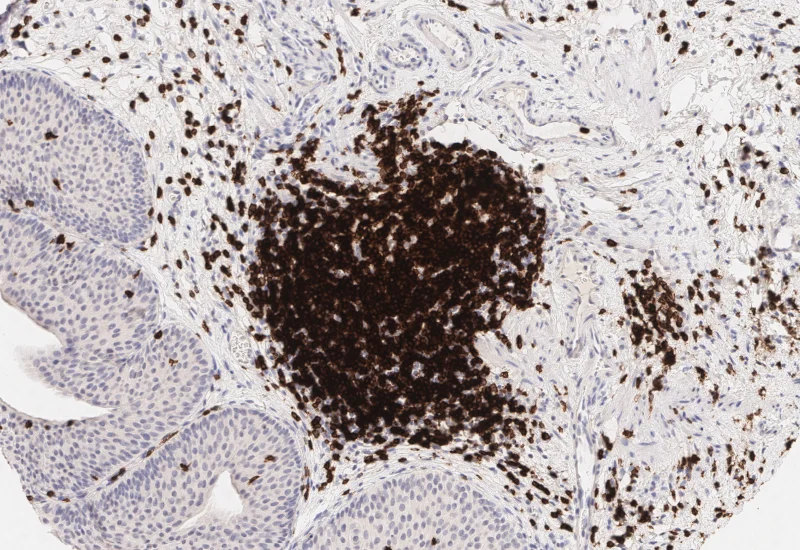

Original Image

Nuclei detection